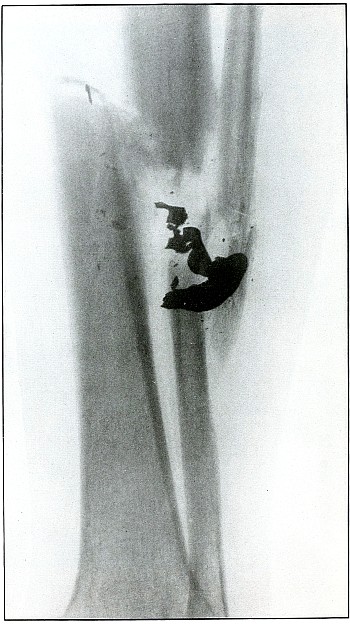

OPERATIVE INTERFERENCE, GUNSHOT WOUNDS. |

157. |

Gunshot fracture, humerus |

324 |

| 158. |

Gunshot fracture, ulna |

326 |

| 159. |

Gunshot fracture, radius and ulna |

328 |

| 160. |

Gunshot fracture, tibia and fibula |

330 |